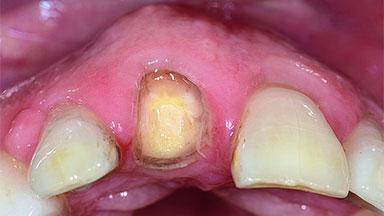

Replacement of an Upper Right Central Incisor with Root Resorption: Ridge Preservation, Early Placement of an RC Bone Level Implant

A 49-year-old female patient was referred for implant therapy to replace the upper right central incisor (tooth 11). The tooth had been assessed by an endodontist who diagnosed a vertical fracture of the root. The tooth had a hopeless prognosis and needed to be extracted. The patient was healthy and was not taking any medications. She was allergic to penicillin. The patient had high esthetic demands but her expectations were realistic. The extraoral examination revealed no facial asymmetries. The right temporomandibular joint demonstrated an opening click but was otherwise asymptomatic. The lip line was high with a significant gingival display.